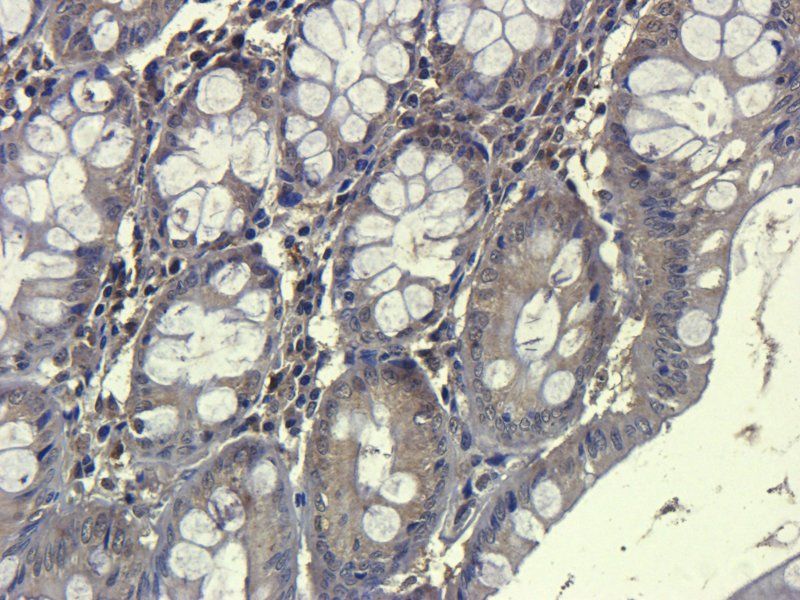

100 μg - FOXP3 antibody [orb34127]Featured

ELISA, ICC, IF, IHC-P, WB

Human, Mouse, Rat

Rabbit

Polyclonal

Unconjugated

100 μg - OPG antibody [orb247239]Featured